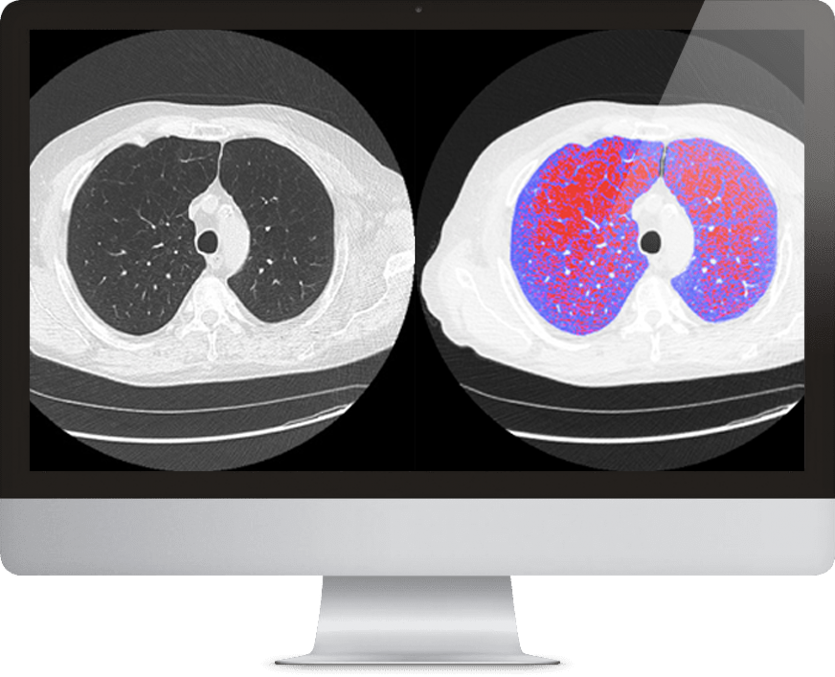

Automated detection of potential Emphysema

LDAi provides fully-automated detection, visualization and quantification of areas of low attenuation (LAA) which can be indicative of emphysema. LDAi is validated for use with low-dose CT scans as a component of lung cancer screening programs and includes a patient-centered LungMap™ report to assist with smoking cessation counseling. LDAi provides results based on a standard inspiratory chest CT.